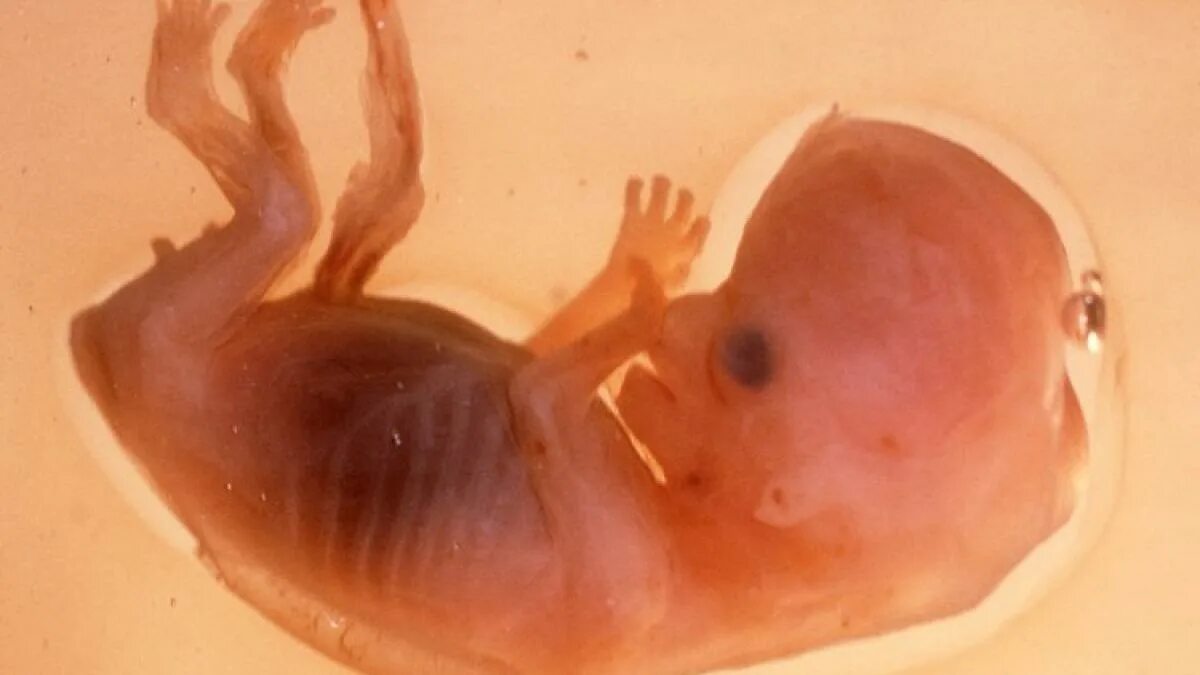

Эмбрион не прикрепился к матке причины